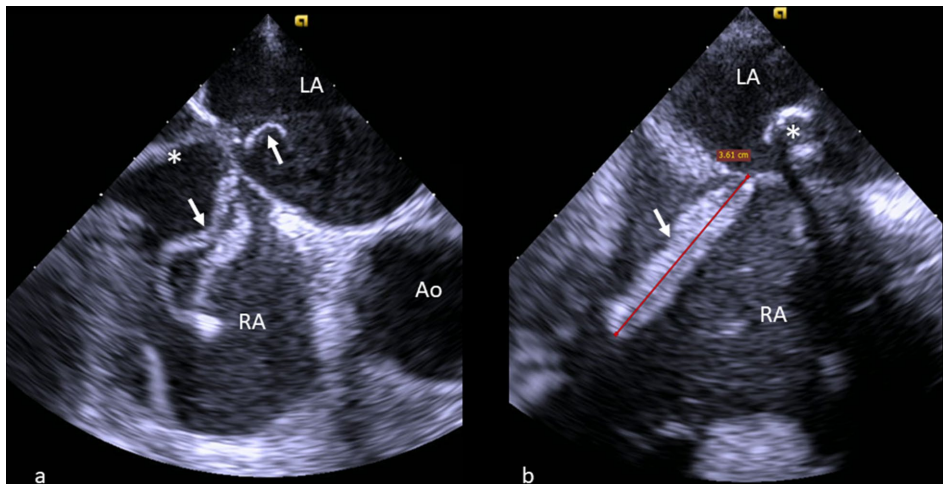

在老龄化社会背景下,二尖瓣反流(Mitral regurgitation)的治疗正经历从外科手术向微创介入的革命性转变。MitraClip作为经导管缘对缘修复术(TEER)的代表性技术,虽能规避开胸风险,但术中血栓形成这一"幽灵"始终萦绕——尤其当24F可操纵导引鞘管(SGC)穿越可能潜伏深静脉血栓的血管时,一场无声的危机便悄然酝酿。意大利莫利塞大学Antonio Totaro团队在《The Egyptian Heart Journal》报道的这例惊险病例,揭开了介入手术中这个被忽视的"阿喀琉斯之踵":83岁男性患者在SGC置入瞬间,经食道超声(TEE)突然捕捉到36mm蛇形模铸血栓盘踞右心房,部分甚至跨越房间隔进入左心房——这种"骑跨型"血栓随时可能引发致死性肺栓塞或脑卒中。

血栓特征与处理策略

ME AV SAX切面显示血栓呈现独特的"模铸"形态(视频2),提示其可能源自未被发现的髂静脉血栓脱落。与常规左心房血栓不同,这种右心房骑跨血栓(7mm突入左心房)具有双重栓塞风险。研究团队放弃抽吸血栓的常规方案,创造性采用"静态处理"原则:固定SGC避免机械扰动,同时通过强化抗凝促使血栓自发溶解(视频4)。